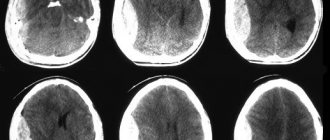

Эпидуральная гематома на компьютерной томограмме имеет вид двояковыпуклой, реже плосковыпуклой зоны повышенной плотности, примыкающей к своду черепа. Гематома имеет ограниченный характер и, как правило, локализуется в пределах одной-двух долей. При венозных источниках кровотечения она может распространяться на значительном протяжении и иметь серповидную форму.

Для субдуральной гематомы на компьютерной томограмме чаще характерно наличие серповидной зоны измененной плотности плосковыпуклой, двояковыпуклой или неправильной формы. Часто субдуральные гематомы распространяются на все полушарие или большую его часть. Внутримозговые гематомы имеют вид круглых или вытянутых зон гомогенного интенсивного повышения плотности с четкими границами. Гематомы формируются как вследствие прямого повреждения сосуда, так и при ангионекрозе в очаге размозжения мозга. Внутрижелудочковые гематомы выявляются зоной интенсивного гомогенного повышения плотности, по своей топике и форме соответствующей тому или иному желудочку мозга.

Внутричерепные кровоизлияния у пострадавших с выраженной анемией могут иметь плотность, одинаковую с плотностью мозга. Для сгустков крови характерна более высокая, чем для жидкой крови, плотность. Они четче дифференцируются от окружающих тканей. Внутричерепные гематомы, содержащие свежую несвернувшуюся кровь, на компьютерной томограмме могут иметь одинаковую с мозгом или даже пониженную плотность, на фоне которой при эпидуральной гематоме может выявляться оттеснение твердой мозговой оболочки.

По мере последующего разжижения содержимого гематом, деградации фибрина в сгустках крови, распада ее пигментов происходит постепенное снижение плотности гематомы, затрудняющее диагностику кровоизлияний, особенно в тех случаях, когда коэффициент абсорбции измененной крови и окружающего мозгового вещества становятся одинаковыми. Затем следует фаза пониженной плотности, в период которой коэффициент абсорбции излившейся крови приближается к плотности цереброспинальной жидкости.